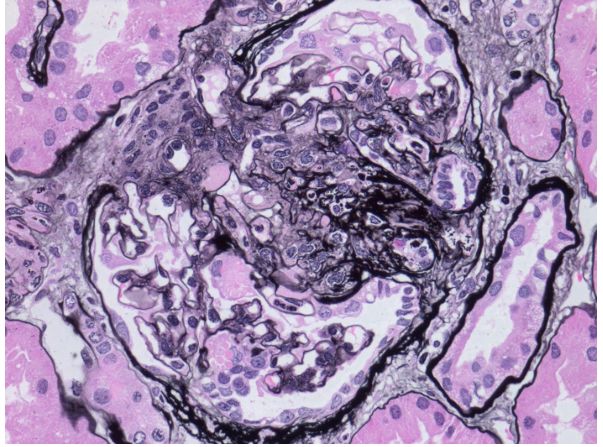

Angry ANCA vasculitis. Pacui immune crescentic GN with exploding glomerulus. Multiple foci of necrotizing arteritis. Fibrinogen staining in necrosis in a crescent and arterial wall. #renalpath #pathsky #nephsky